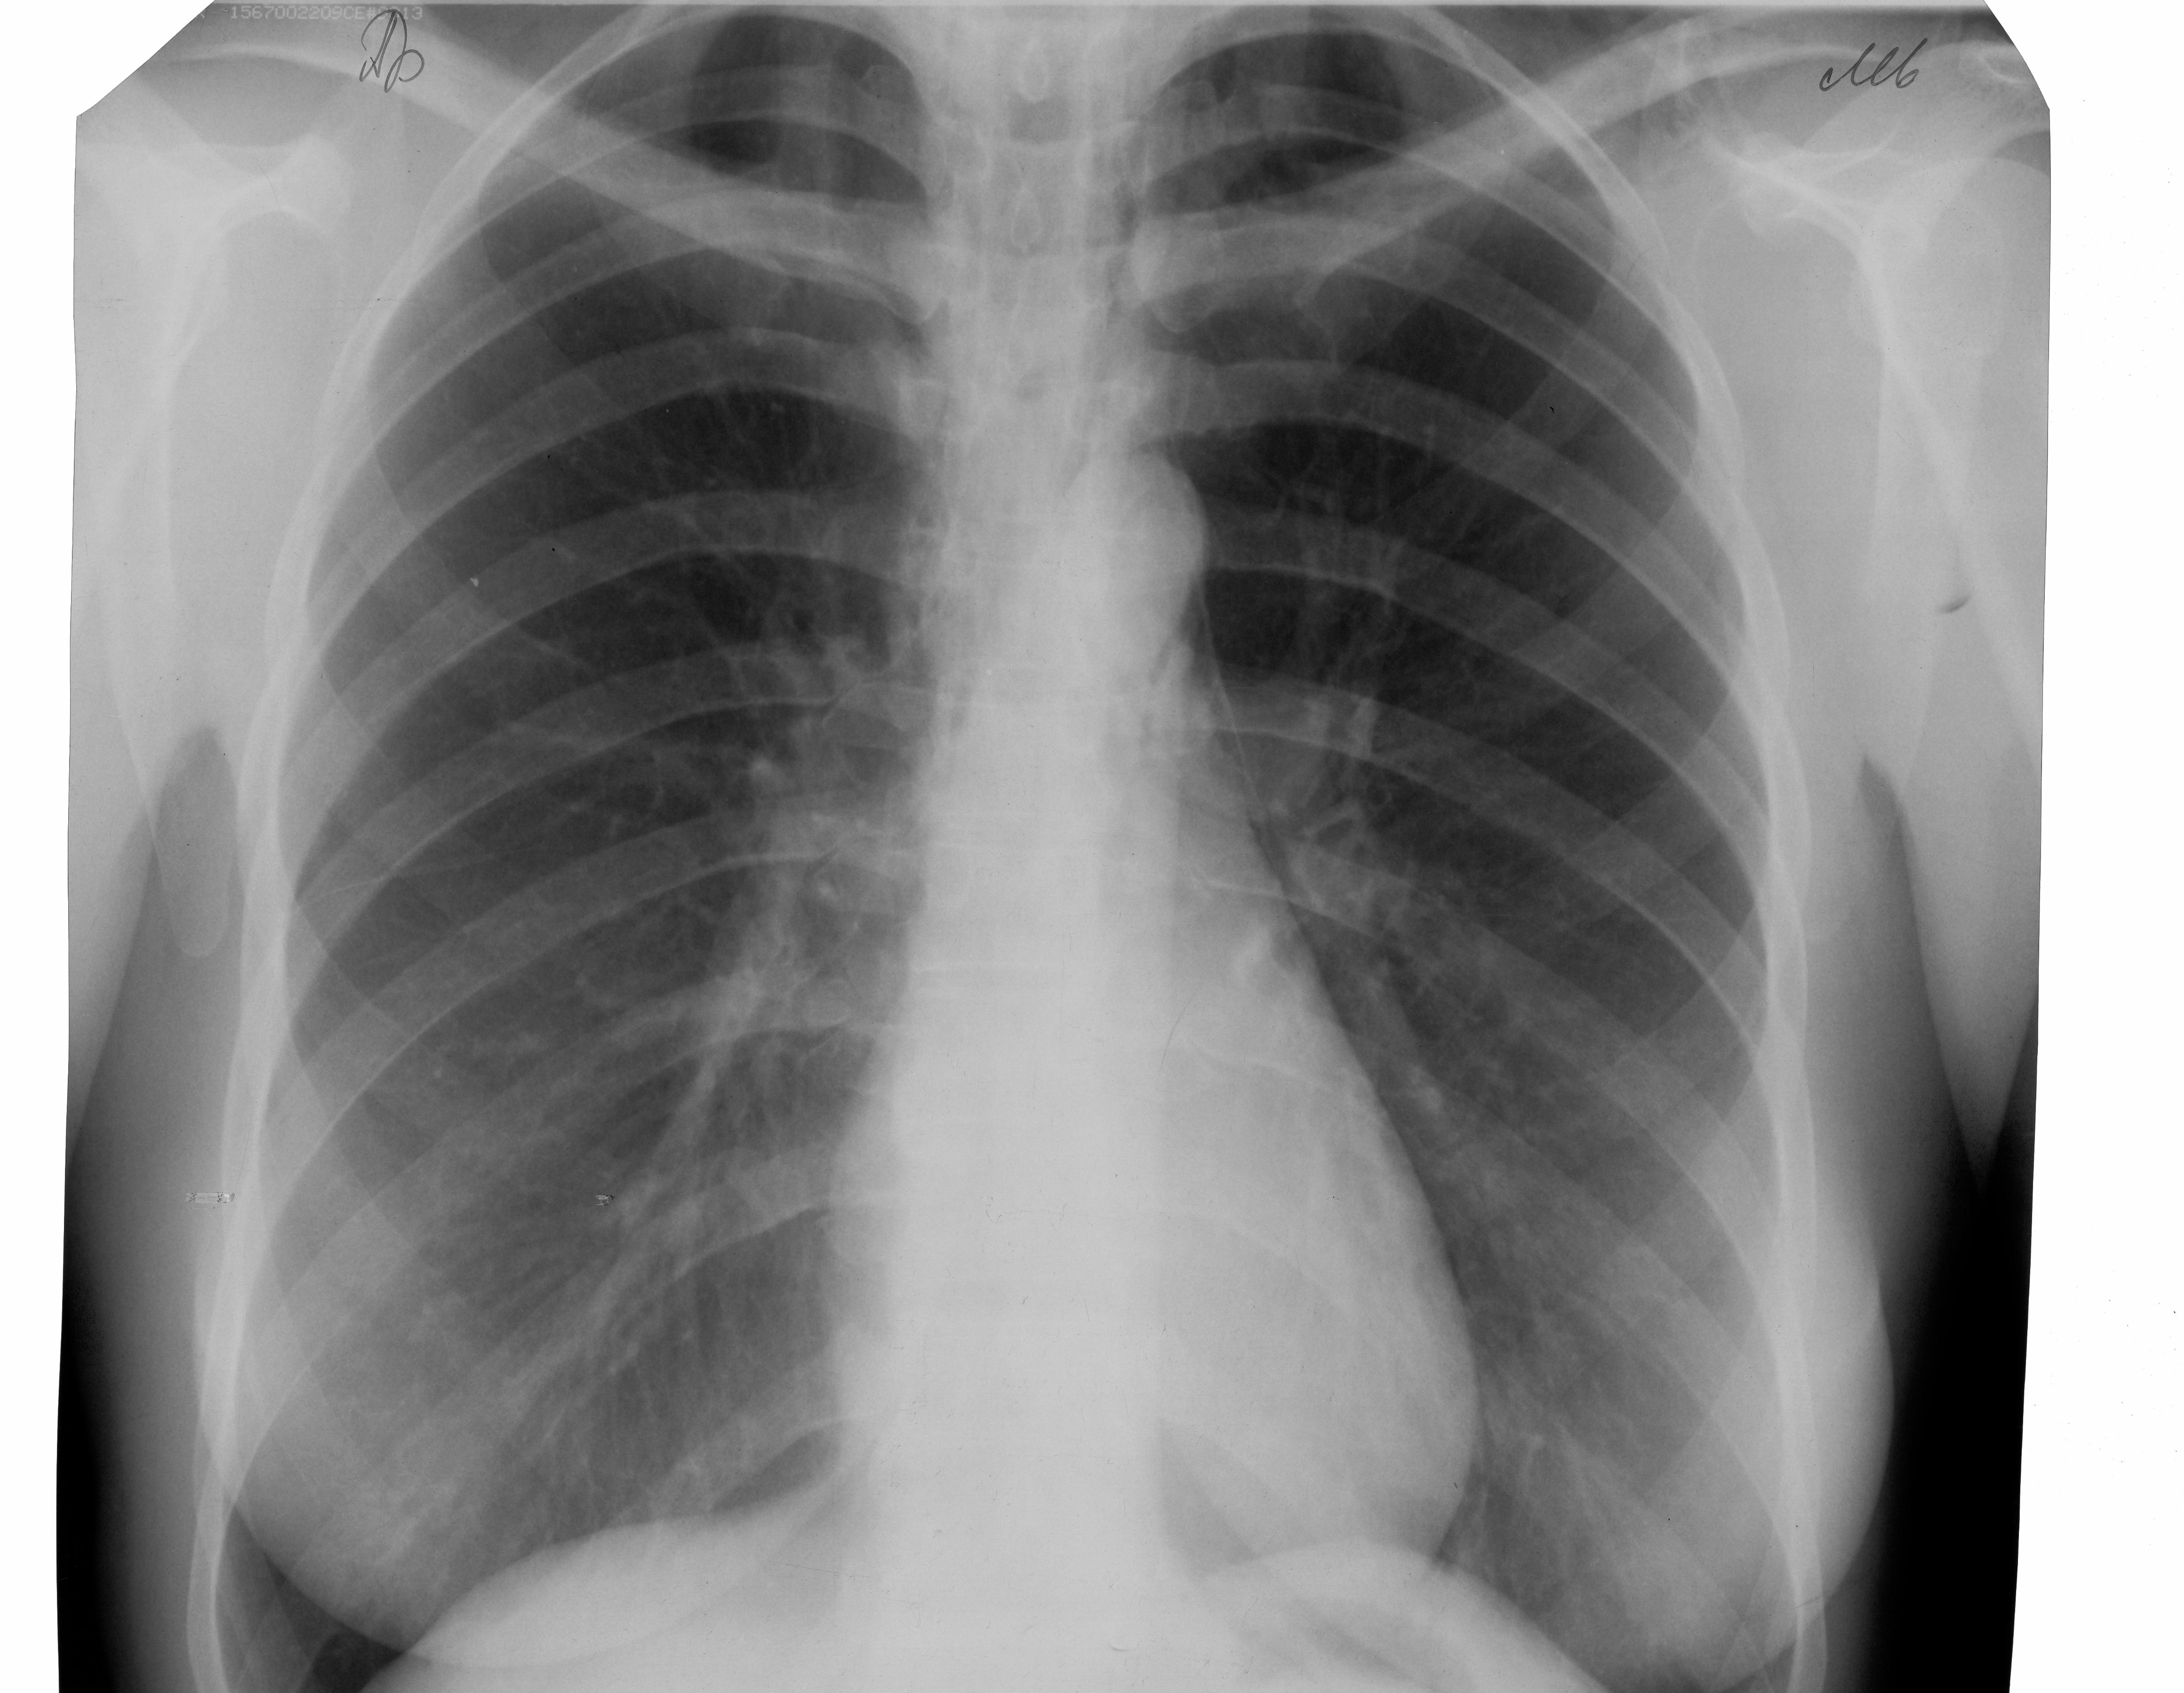

Женщина, вернулась из леса с пикника.Жалобы на боли за грудиной, шее, связанные с движением, осиплость голоса,одышка. Боковой снимок не делали. https://radiomed.ru/sites/default/files/styles/case_slider_image/public/user/18473/pnevmomediast00002.jpg?itok=bnYDKqfS ID:48350 Чт, 29/08/2013 - 14:38 #1 Helios Не на сайте Был на сайте: 7 месяцев 2 недели назад Зарегистрирован: 06.08.2010 - 15:16 Публикации: 4417 Исправила. Забыли на кнопочку нажать. Чт, 29/08/2013 - 14:42 #2 Helios Не на сайте Был на сайте: 7 месяцев 2 недели назад Зарегистрирован: 06.08.2010 - 15:16 Публикации: 4417 Это воздух в превертебральном пространстве ? Чт, 29/08/2013 - 14:53 #3 Сергей Рожков Не на сайте Был на сайте: 11 лет 11 месяцев назад Зарегистрирован: 23.12.2010 - 06:22 Публикации: 9 выраженная эмфизема предпозвоночных мягких тканей, пневмомедиастенеум. Не исключается перфорация пищевода. Что-то острое кушала? Чт, 29/08/2013 - 15:03 #4 Helios Не на сайте Был на сайте: 7 месяцев 2 недели назад Зарегистрирован: 06.08.2010 - 15:16 Публикации: 4417 У меня подобный случай был 2 года назад, после травмы. Чт, 29/08/2013 - 15:49 #5 медсанчасть рег... Не на сайте Был на сайте: 11 лет 1 месяц назад Зарегистрирован: 11.06.2013 - 10:46 Публикации: 136 решили выложить как новый случай Чт, 29/08/2013 - 15:34 #6 Helios Не на сайте Был на сайте: 7 месяцев 2 недели назад Зарегистрирован: 06.08.2010 - 15:16 Публикации: 4417 Снимочки интересные, даже фамилия мелькаетНадо исправить. Чт, 29/08/2013 - 15:43 #7 медсанчасть рег... Не на сайте Был на сайте: 11 лет 1 месяц назад Зарегистрирован: 11.06.2013 - 10:46 Публикации: 136 а как удалить и заменить снимки Чт, 29/08/2013 - 17:04 #8 Helios Не на сайте Был на сайте: 7 месяцев 2 недели назад Зарегистрирован: 06.08.2010 - 15:16 Публикации: 4417 Лучше в отдельной теме, предварительно убрав данные пациента. Чт, 29/08/2013 - 18:30 #9 Nikolas Не на сайте Был на сайте: 1 месяц 3 недели назад Зарегистрирован: 21.12.2010 - 20:37 Публикации: 4559 вяленой рыбки Надо вытаскивать. Чт, 29/08/2013 - 20:43 #10 медсанчасть рег... Не на сайте Был на сайте: 11 лет 1 месяц назад Зарегистрирован: 11.06.2013 - 10:46 Публикации: 136 Дообследована в тор.хирургии,проведена ФГС,ФБС,причина не установлена. Чт, 29/08/2013 - 21:48 #11 Nikolas Не на сайте Был на сайте: 1 месяц 3 недели назад Зарегистрирован: 21.12.2010 - 20:37 Публикации: 4559 пациентки? Чт, 29/08/2013 - 23:12 #12 Almo Не на сайте Был на сайте: 1 день 4 часа назад Зарегистрирован: 28.09.2008 - 18:50 Публикации: 8248 Дообследована в тор.хирургии,проведена ФГС,ФБС,причина не установлена. ----------------------------------------------------------------------------------------------------------------------------------------- А, пнемомедиастинум разрешился? И какая может быть дальнешая тактика обследования пациентки? Пт, 30/08/2013 - 11:34 #13 медсанчасть рег... Не на сайте Был на сайте: 11 лет 1 месяц назад Зарегистрирован: 11.06.2013 - 10:46 Публикации: 136 Возраст 48 лет.Со слов хирурга пневмомедиастинум клинически и рентгенологически разрешился.Дальнейшая тактика-динамическое наблюдение. Пт, 30/08/2013 - 13:09 #14 Almo Не на сайте Был на сайте: 1 день 4 часа назад Зарегистрирован: 28.09.2008 - 18:50 Публикации: 8248 Спасибо!

Это воздух в превертебральном пространстве ?

выраженная эмфизема предпозвоночных мягких тканей, пневмомедиастенеум. Не исключается перфорация пищевода. Что-то острое кушала?

Дообследована в тор.хирургии,проведена ФГС,ФБС,причина не установлена.

А, пнемомедиастинум разрешился? И какая может быть дальнешая тактика обследования пациентки?

Возраст 48 лет.Со слов хирурга пневмомедиастинум клинически и рентгенологически разрешился.Дальнейшая тактика-динамическое наблюдение.